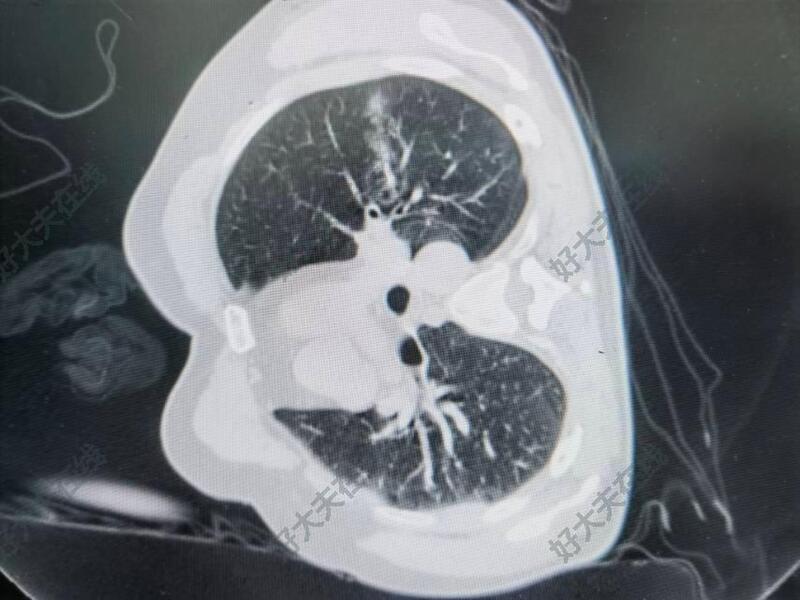

治疗后

- 治疗后即刻

患者顺利完成消融治疗,治疗后消融范围确切,充分覆盖肿瘤。